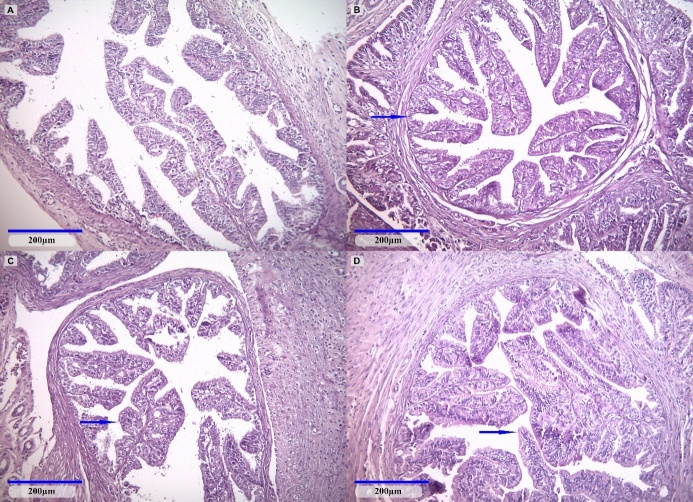

The current study aimed to assess the possible endocrine disruptor effects on rat mammary tissue and reproductive organs during pregnancy and lactation when exposed to low doses of glyphosate and its combination with 2,4-dichlorophenoxyacetic acid (2,4-D) and dicamba. The study involved the exposure of pregnant Wistar rats to various regulatory-relevant doses of glyphosate, ranging from gestational day 6 until fine of the lactation period. Glyphosate doses corresponded to the European Union's glyphosate-acceptable daily intake (ADI; 0.5mg/kg bw/day) and no observed adverse effect level (NOAEL; 50mg/kg bw/day). The dose of the mixture of glyphosate, dicamba, and 2,4-D was at the European Union ADI for each herbicide namely 0.5, 0.002, and 0.3mg/kg bw/day, respectively. In the animals exposed to glyphosate NOAEL serum estradiol levels were increased compared to untreated animals, along with an upregulation of TNF-?, MMP-2, and MMP-9 as measured in mammary gland homogenates compared to non-treated animals. Moreover, in this group, a focally acute inflammatory infiltrate was observed in the mammary gland. Our study showed that short-term exposure to glyphosate at doses that are set as safe by regulators and thus without risk corroborated with a particular physiological state as gestation and lactation, can give rise to inflammatory changes in breast tissue in rats. These findings support the need for further evaluation of glyphosate and mixtures of glyphosate with other pesticides for public health protection, especially for those categories vulnerable to the potential endocrine disruptor properties of these pesticides such as pregnant women, newborns, and children.